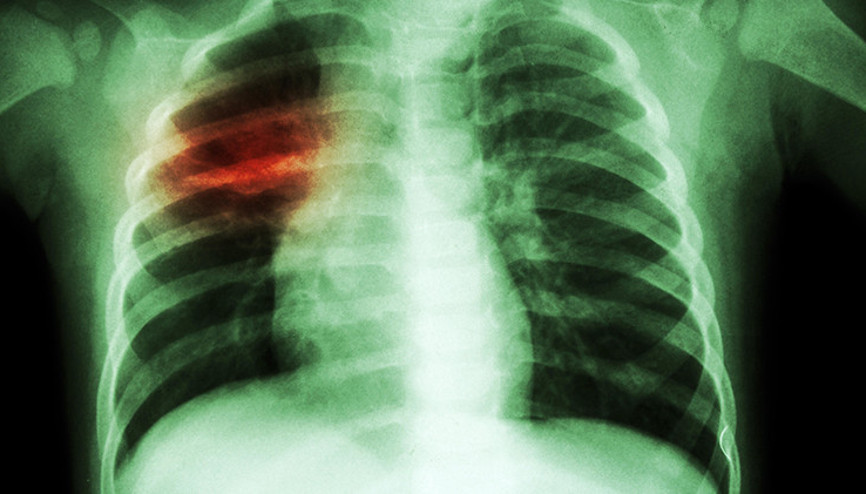

#VeremSon zamanlarda koronavirüs korkusu nedeniyle hastanelere başvuru ve teşhis sayılarında düşüş yaşandığını belirten uzmanlar, verem hastalarının artabileceğine dikkat çekiyor. Göğüs Hastalıkları Uzmanı Prof. Dr. Muhammed Akkoyunlu, “İşin özüne baktığımızda tüberküloz ve kovid-19 aslında birbirinden çok farklı hastalıklar. Kısmi de olsa bazı belirtiler ortak. Mesela öksürük, halsizlik, kırgınlık, ateş gibi belirtileri örnek gösterebiliriz. Dolayısıyla bazen tüberküloz hastaları ile koronavirüs hastaları benzer semptomlar nedeniyle karıştırılabilir. Hatta, eğer tüberkülozun erken dönemi ise akciğer görüntüleri de karışabilir” dedi.

#TüberkülozVerem hastalığının en sık akciğerlerde görüldüğünü belirten Prof. Dr. Serdar Erturan, "2-3 haftadan uzun süre öksürük, balgam, ateş, gece terlemeleri, iştahsızlık, kilo kaybı, yorgunluk, halsizlik, soluk darlığı, göğüs ve sırt ağrısı, akciğer dışı verem hastalığı olanlar da o organa ait farklı belirtiler olabilir" dedi.